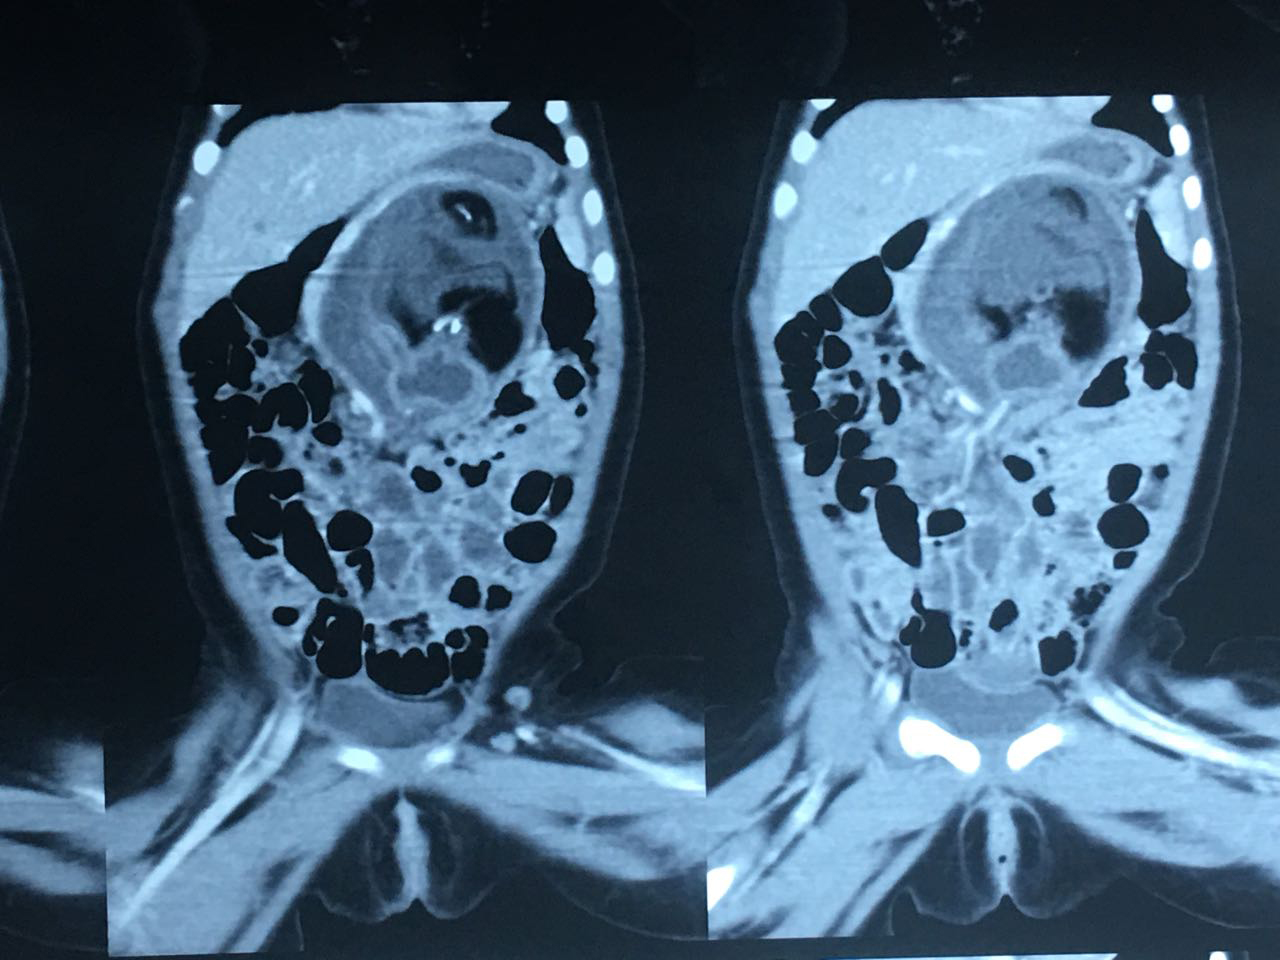

Foetus-In-Fetu (3)